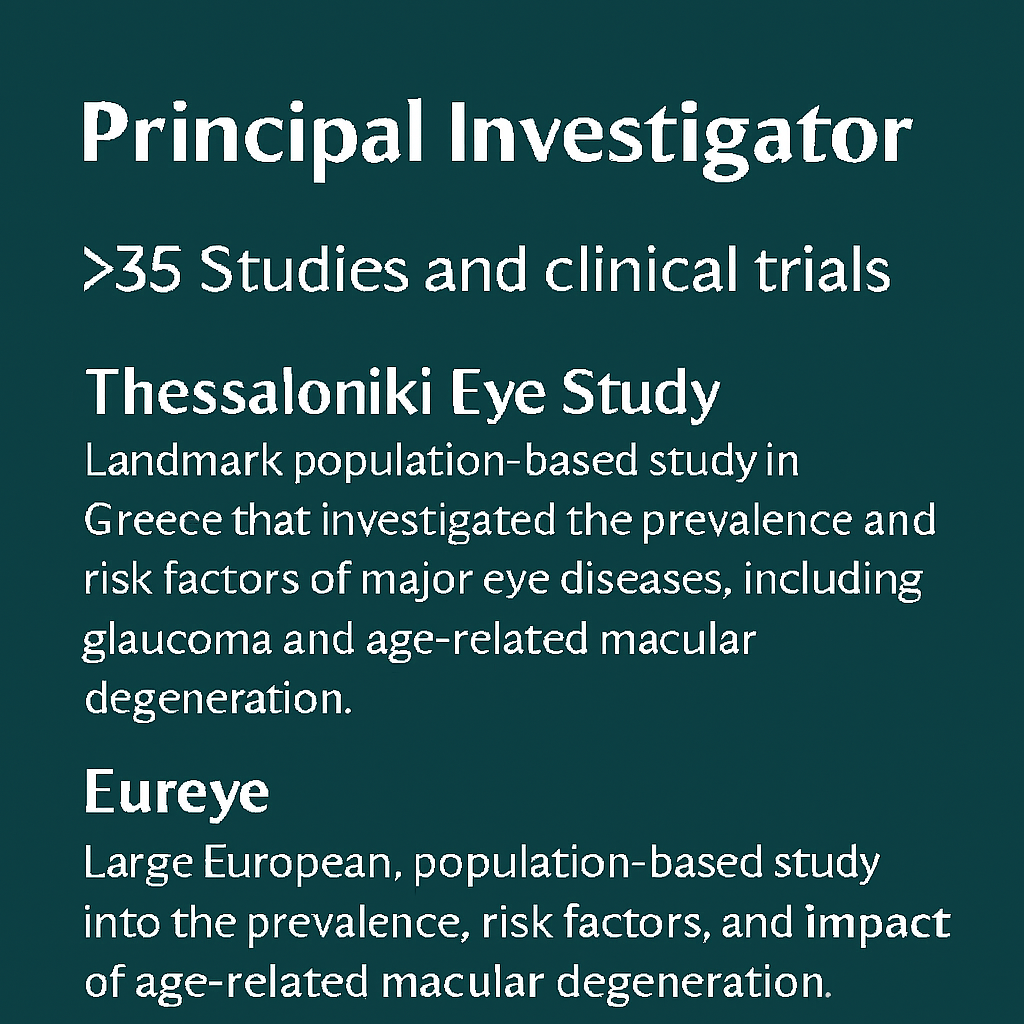

Research interest includes epidemiology, clinical and genetic research in ophthalmic disease with focus in glaucoma, age related macular degeneration and diabetic retinopathy.